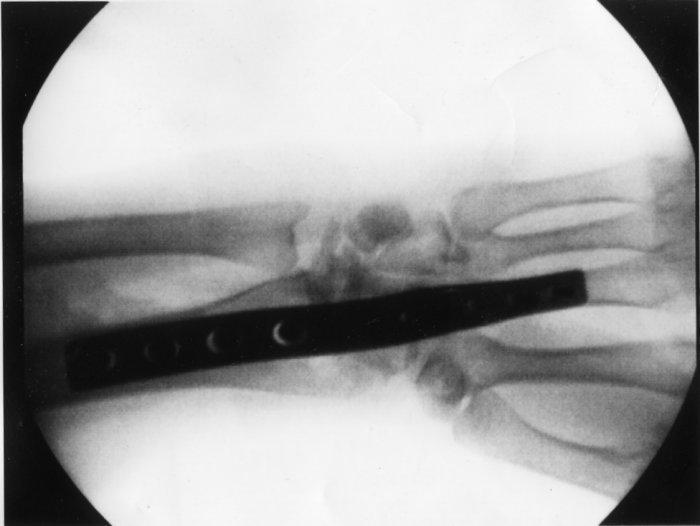

Bledsoe Brace Xray with Plate

4 Weeks Post-Op Plate and Screws